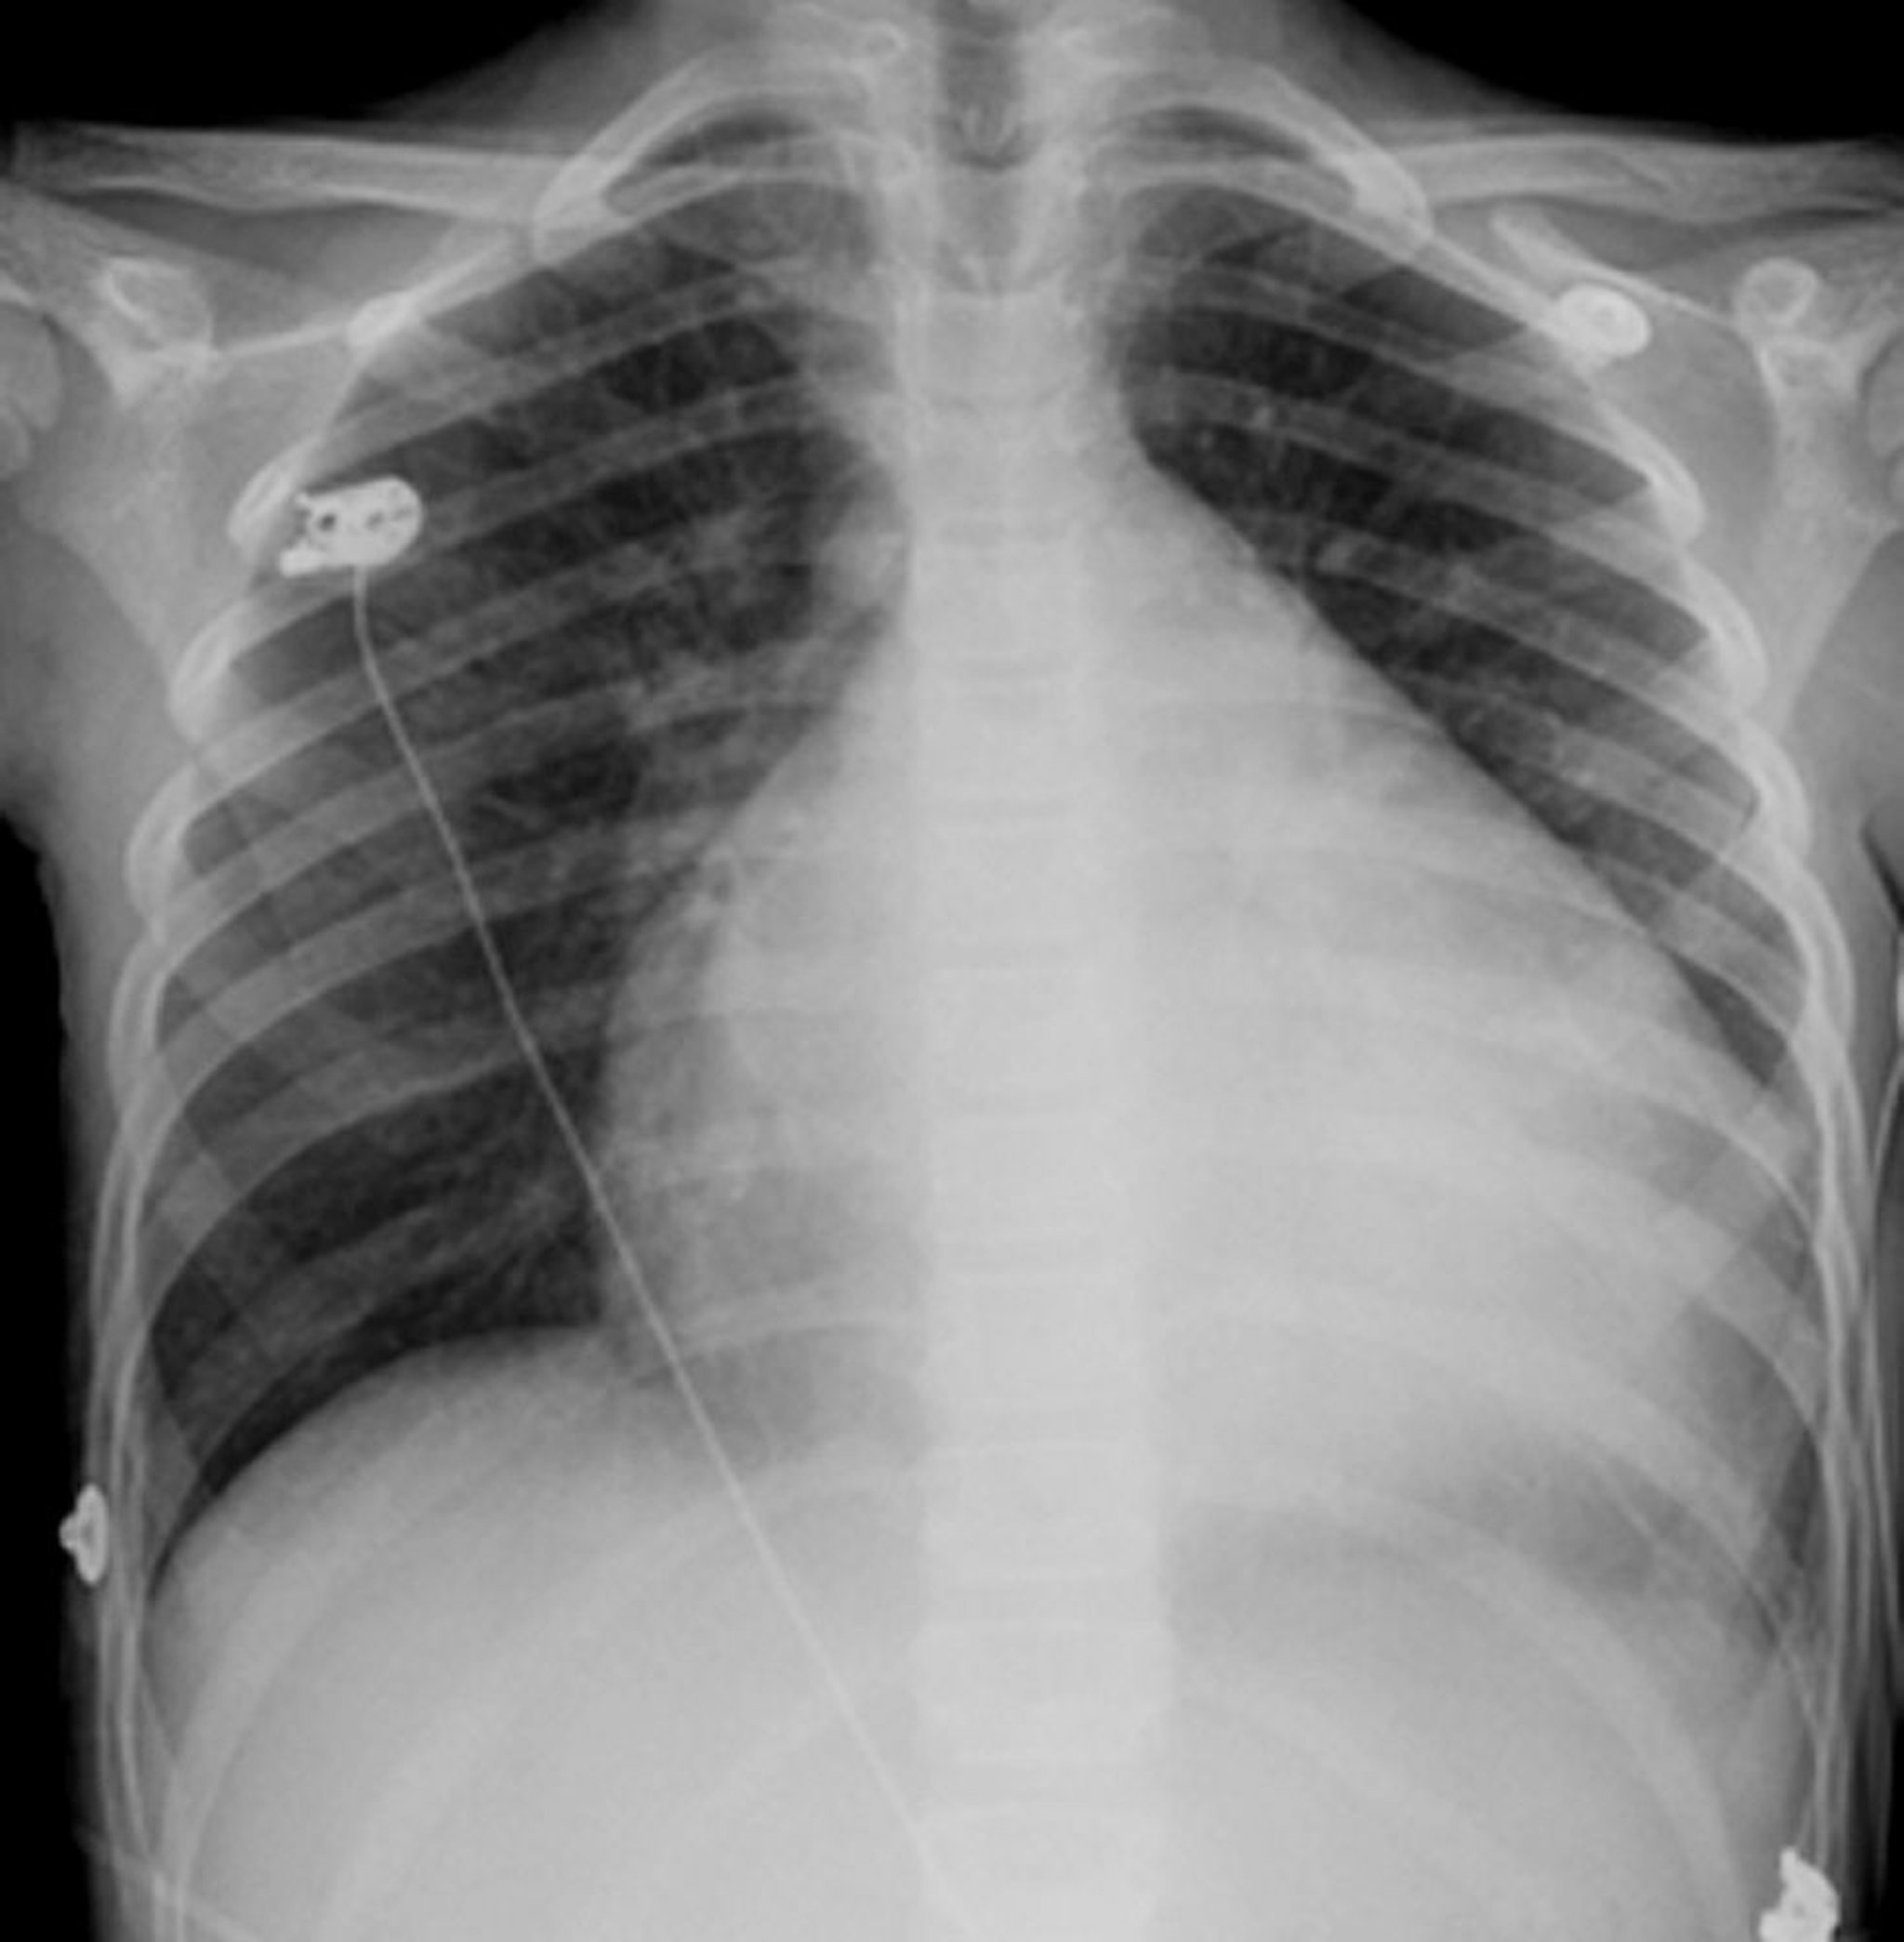

心拡大

胸部の中央にみられる、球状で白い構造物が心臓です。心臓は通常、胸部の半分未満のスペースに収まっていますが、心拡大(心筋症)の場合には、胸部直径のほぼ4分の3を占めます。